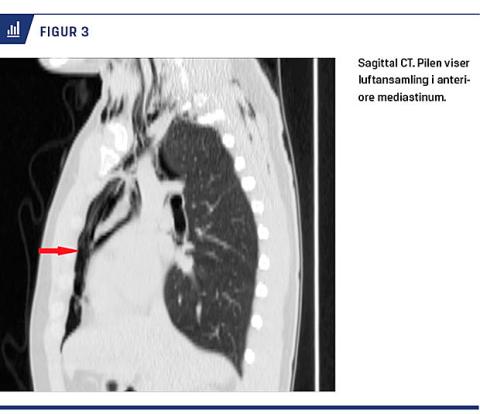

SME kan i 75-90% af tilfældene diagnosticeres på en almindelig røntgenoptagelse af thorax [1, 7, 8, 13]. På sidebilledet kan et tegn på fri luft i mediastinum være en ring rundt om selve a. pulmonalis eller en af dens større grene. Der kan desuden ses luft mellem sternum og den anteriore hjertevæg, det såkaldte pneumoprækardiale tegn. På frontalbilledet kan der observeres luftstrøg i den superiore mediastinum, fremtrædende hjertesilhuet og subkutant emfysem op langs hals og nakke (Figur 1) [5].